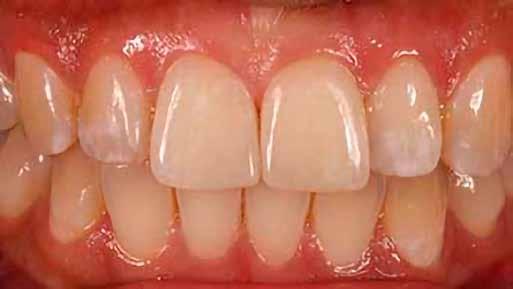

14. ábra: Egy moláris fog preoperatív állapota.

15. ábra: Egy moláris fog postoperatív fotója.